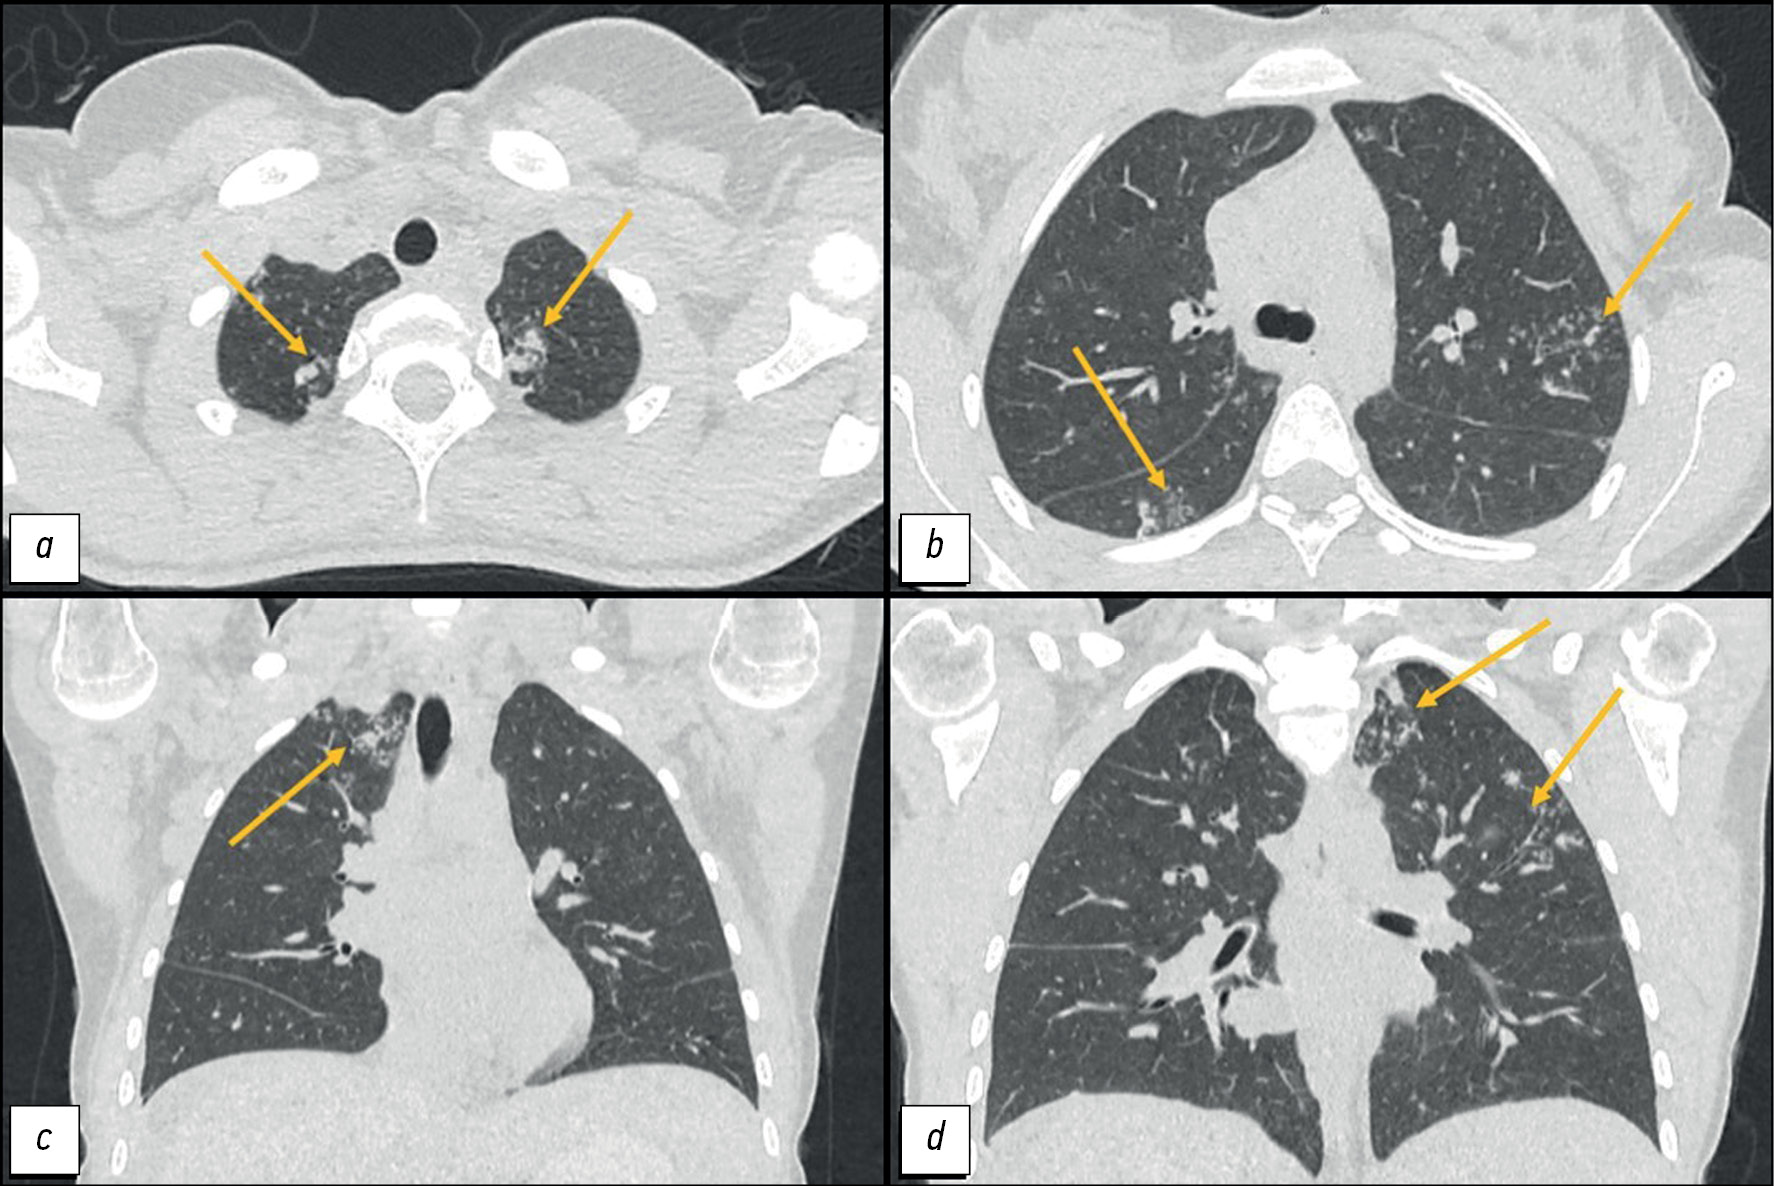

文章描述了对一名年轻患者的临床观察。第二次分娩后,患者发现了肩胛骨之间的颈部出现剧烈疼痛。随后,在出现症状两个月后,患者患上了肺炎,并对抗生素治疗产生了积极反应。两个月后,她首次发现了反复腹水和胃肠道症状。检查发现了卵巢病变、腹膜转移癌征候以及肺部病灶。然而,腹膜转移癌的临床表现并不典型,而且肺部有特殊病变,因此怀疑是多部位结核。通过腹腔镜检查和受影响组织的活检,以及随后的组织学和实验室检查,确诊为Mycobacterium tuberculosis。